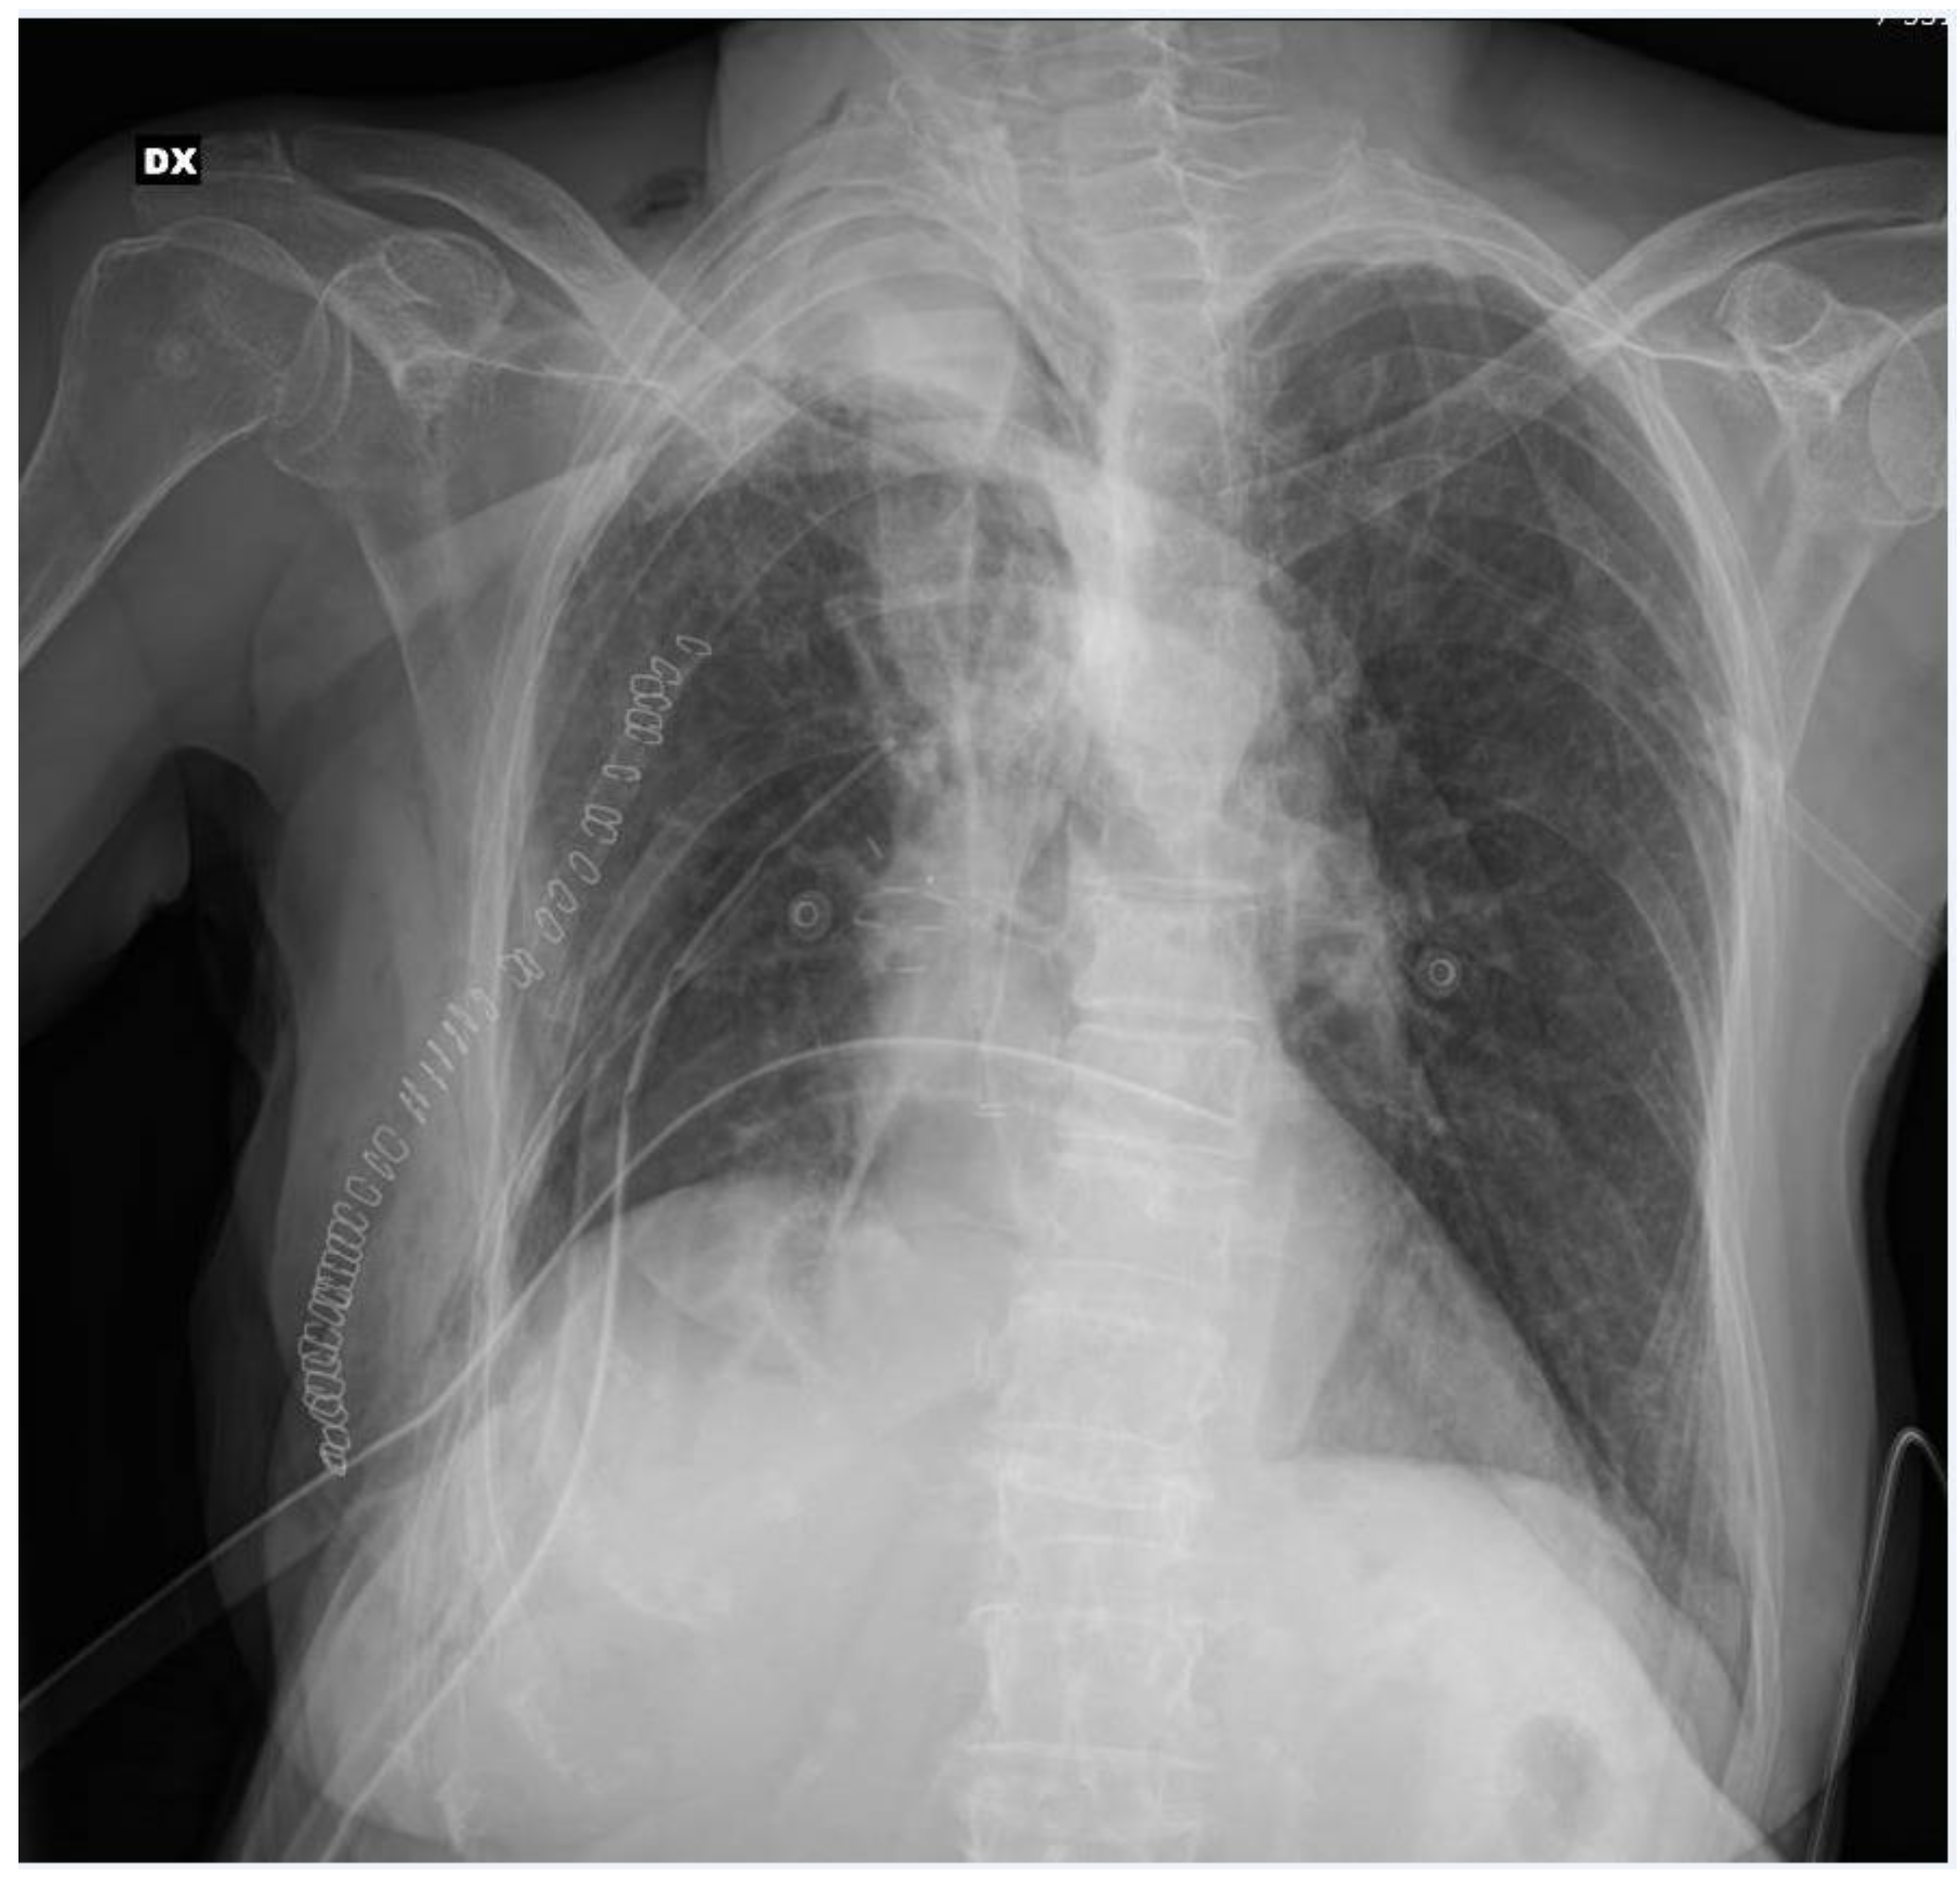

After the multidisciplinary oncology tumor board reviewed the case, the patient became a candidate for lung surgery. Extrapleural lower bilobectomy with the removal of the VI rib was performed via posterolateral thoracotomy. The surgery lasted 205 min with no intraoperative complications; two chest tubes were positioned at the end of the operation. Pathological analysis diagnosed a “poorly differentiated adenocarcinoma with a solid pattern, infiltrating the parietal pleural, with widespread neoplastic embolization, pT4N1G3”. After the surgical procedure, the patient was admitted to our sub-intensive care unit for multiparameter monitoring. The patient required a blood transfusion on the day of surgery. The postoperative bedside chest X-ray showed incomplete lung expansion (Figure 2).

Figure 2.

Post-operative chest X-ray.